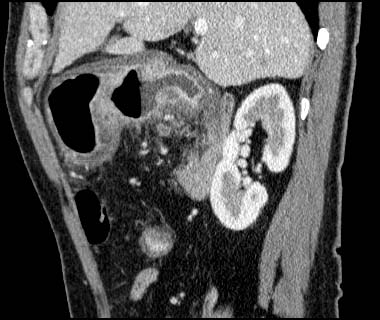

Gastric cancer / Borr.III

1mmx4, Pitch 4.5, 23 seconds, 150mAs

Sagittal MPR

Data acquired & processed by H. Anno M.D.